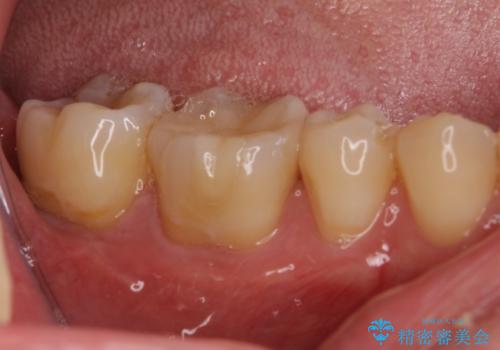

古い材料も虫歯もすべて除去して、根本からやりかえました。

セラミックが欠けるほど強い力がかかっているということは、ご自身の歯も割れている(小さいヒビ等も含む)可能性があります。拡大鏡でしっかり見ながら治療します。

咬む力が強いため、このままでは何度もセラミックとご自身の歯を割る可能性就寝時マウスピースの使用をご提案しました。患者様には、大変満足して頂きました。